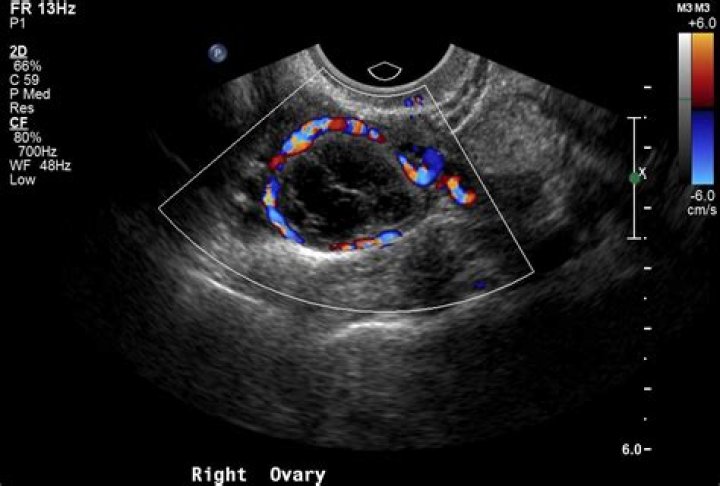

Recent Improvements in the Sonographic Detection of Ovarian Cancer

What does red mean on an ultrasound?

By definition, flow towards the transducer is depicted in red while flow away from the transducer is shown in blue. Different shades of red and blue are used to display velocity. Lighter shades of color are assigned to higher velocities.

However, to evaluate the presence and direction of blood flow in the heart and vessels, color Doppler ultrasound has been used. Color Doppler displays blood flow in two basic colors. Red or Red-Orange displays blood flowing towards the top of the screen, and Blue displays flow towards the bottom of the screen.

What do red and blue colors mean on ultrasound?

Vessels in which blood is flowing are colored red for flow in one direction and blue for flow in the other, with a color scale that reflects the speed of the flow. Because different colors are used to designate the direction of blood flow, this Doppler technique simplifies interpretation of the ultrasound data.

What do colors on an ultrasound mean?

Typically, red and blue colors are used to highlight the blood flow in one direction or the other regarding the probe's position. The speed of the blood flow is shown with a color scale. Usually, blood flow away from the probe is shown in blue, while blood flow toward the probe is red.

What do malignant ovarian cysts look like on ultrasound?

The most consistent sonographic signs of malignancy appears to be the presence of papillary excrescences > 3 mm along the internal wall of an ovarian mass and the presence of a solid component21.